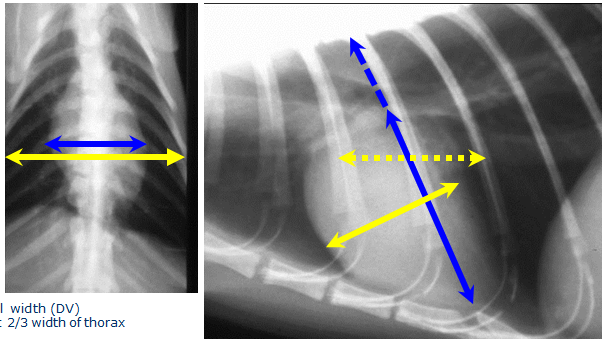

What is the normal size of a dogs heart?

Normal width (DV)

–< 2/3 width of thorax

Normal width (lateral)

–2.5 – 3.5 intercostal spaces wide

Normal height (lateral – 5th rib)

–2/3 height of thorax

What is the vertebral heart score?

Add the no. of vertebrae

Suggested normal range

= 8.5 – 10.5

Breed specific values available

•Normal ranges differ between breed so always refer to this